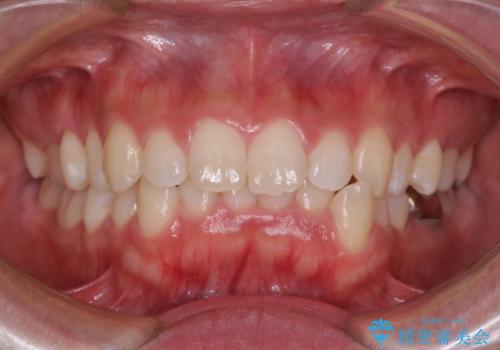

- 前歯のデコボコやクロスバイト、口元の突出感を気にして来院された患者様です。

上下左右の第一小臼歯4本を抜歯して、ワイヤー装置にて矯正治療を行うこととしました。

途中出産や育児があり、治療期間長くなってしまいましたが、ストレスなく唇が閉じられるような口元に仕上げることができました。